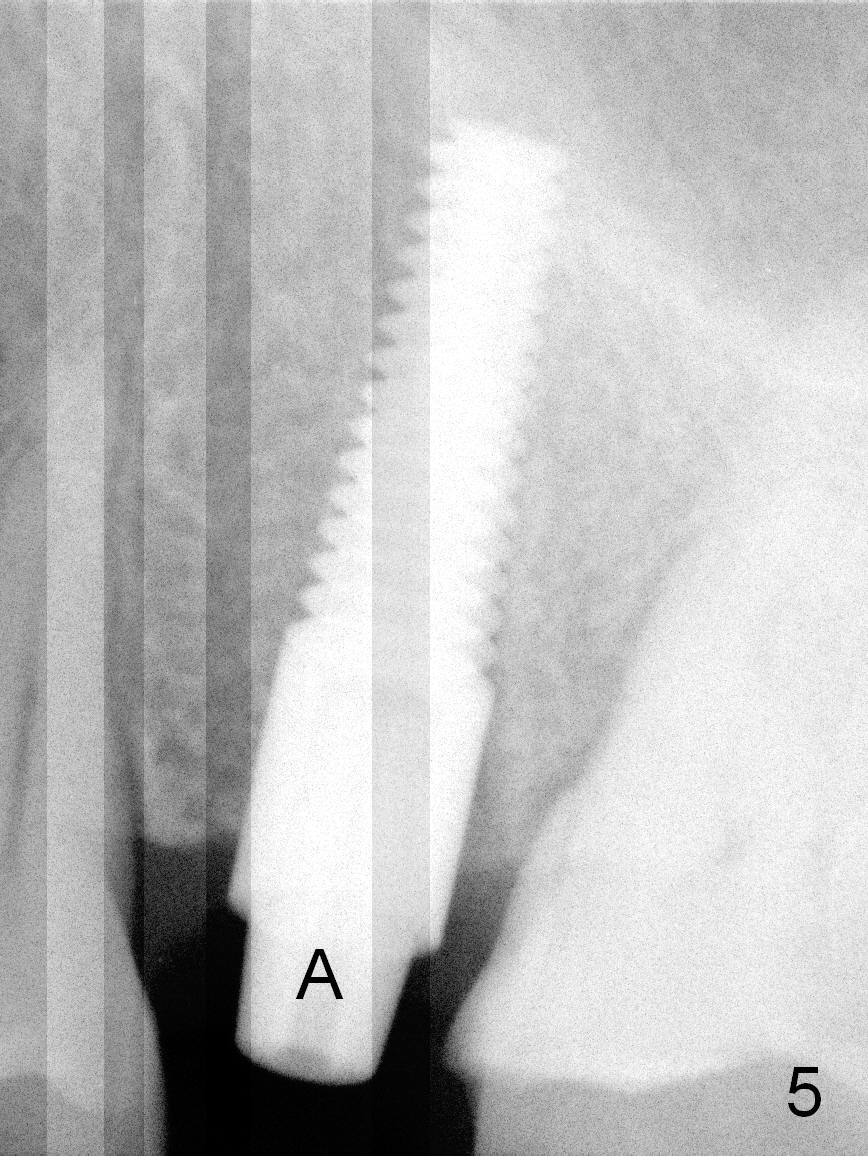

A 47-year-old man returns to clinic with chief complaint "top left tooth chips". Exam reveals subgingival fracture of the lingual cusp of the tooth #13 (Fig.1). A 4.5x17 mm tissue-level implant and 3.5x3 mm abutment appear to be appropriate for the site (Fig.2 (^: sinus floor)). After extraction and socket treatment with 1:50,000 Epinephrine gauze, a 4.5x20 mm tap is placed at the depth of 17 mm. Although the tap has achieved stability, a PA taken with it does not the superior end due to the interference of its long handle (Fig.3 H). A dummy implant (4.5x17 mm) is placed to show its approximation to the sinus floor (Fig.4). After removal of the dummy implant, the definitive implant is placed with certainty with the planned abutment (Fig.5 A). An immediate provisional is placed after bone graft and membrane.